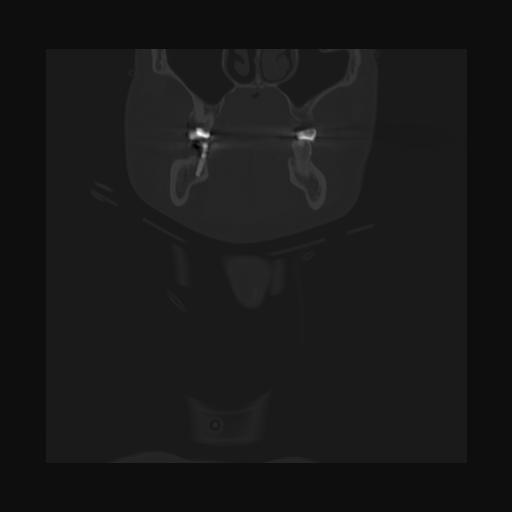

16 HUESO,,Coronal,2.000,HUESO,Coronal,